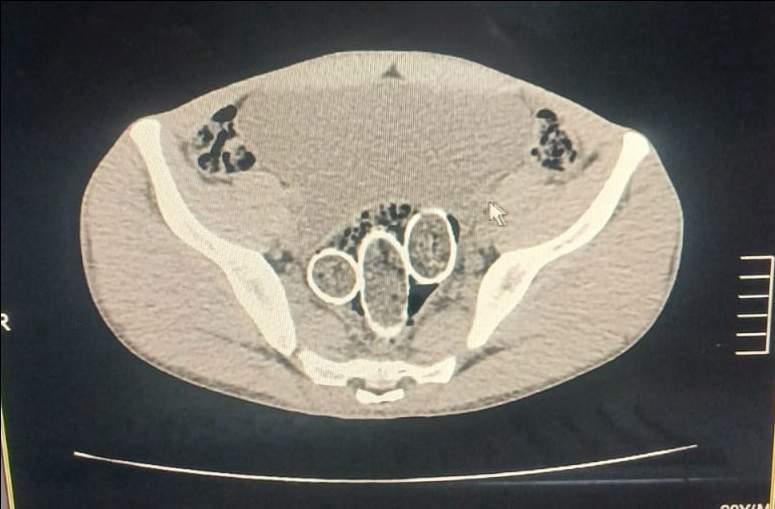

Denizli İl Emniyet Müdürlüğü Narkotik Suçlarla Mücadele Şube Müdürlüğü ekipleri, uyuşturucu ticaretine yönelik yürüttüğü çalışmalarda bir şebekeyi takibe aldı. Eş zamanlı baskınlarda yakalanan beş şüpheliden ikisinin mide ve rahim bölgelerinde uyuşturucu taşıdığı belirlendi. Yapılan iç beden muayenelerinde, altı paket halinde toplam 320 gram metamfetamin maddesi ele geçirildi.

OPERASYONDA ŞOKE EDEN DETAYLARDenizli İl Emniyet Müdürlüğü Narkotik Suçlarla Mücadele Şube Müdürlüğü ekipleri, uyuşturucu ticaretine yönelik yürüttüğü çalışmalarda bir şebekeyi takibe aldı. Eş zamanlı baskınlarda yakalanan beş şüpheliden ikisinin mide ve rahim bölgelerinde uyuşturucu taşıdığı belirlendi. Yapılan iç beden muayenelerinde, altı paket halinde toplam 320 gram metamfetamin maddesi ele geçirildi.